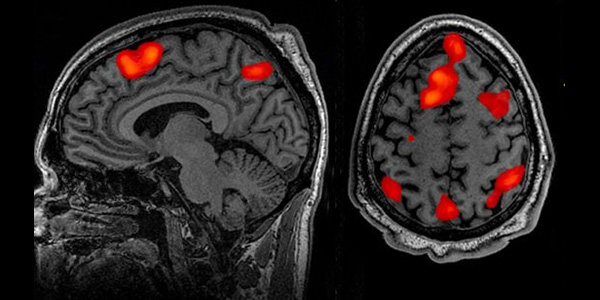

In epoca storica, il primo a scrivere di isteria è stato Ippocrate che era convinto che si trattasse di una malattia relativa ai disturbi dell’utero e sosteneva che «l’utero fosse la causa di tutti i mali delle donne». Essendo un organo asciutto e cavo, assorbirebbe una quantità maggiore di sostanze rispetto all’uomo, causando l’accumulo di liquido poi espulso sotto forma di sangue mestruale; era persuaso che la donna per riequilibrare le differenze di umidità dell’utero avrebbe avuto spesso bisogno del coito. Poteva accadere, secondo Ippocrate, che questo equilibrio si interrompesse, così l’utero rimanendo asciutto si spostava nel ventre e provocava dolore e «soffocazione interna», ovvero una sensazione di soffocamento e di confusione mentale e ciò accadeva solamente a quelle che non avevano avuto rapporti sessuali e alle anziane. L’intendimento di Ippocrate, considerando lo sviluppo della scienza medica del periodo, non fu quello di imprimere un marchio alle donne, purtroppo però le sue parole, successivamente, sono state strumentalizzate. Ancora oggi una donna, se nervosa o mette in discussione quanto le viene detto anche durante un tranquillo dialogo tra amici, è consapevole che prima o poi si sentirà dire «hai le tue cose?», come se la capacità di dibattito dipendesse da quello che accade nelle nostre pelvi. Queste frasi si trascinano da secoli di pregiudizio, pseudoscienza e misoginia. Nel Medioevo l’isterica cambia identità, i sintomi assumono un significato diverso, nelle biografie delle mistiche, l’anoressia, il mutismo, le assenze mentali, le allucinazioni sono descritte come prove di santità. Però nei processi alle streghe vi sono riferimenti a sintomi isterici, tanto da usarli come prova palese di forze sovrannaturali siano esse divine o diaboliche, non più come avveniva nella medicina ginecologica precristiana, in questo caso il medico veniva sostituto dall’esorcista. La natura scientifica dell’isteria inizia a essere studiata nel XVII secolo, quando Charles Lepois ha spostato la causa di questo disturbo dall’utero al cervello, nello stesso periodo il medico inglese Thomas Sydenham ha sostenuto l’importanza delle emozioni nella genesi della malattia, considerandola uno squilibrio tra mente e corpo, anche se gli venne difficile mantenere la sua posizione, soprattutto, nelle sintomatologie collettive epidemiche di disagio sociale. Via via, l’isteria in quanto enigmatica generò un conflitto di competenze, dal quale nascerà una nuova disciplina medica: la psichiatria. Nel 1656 il re di Francia Luigi XIV fece costruire l’ospedale Salpêtrière di Parigi, inizialmente considerato come opera di carità per i/le mendicanti e le persone emarginate, ampliato nel 1680 per accogliere prostitute e donne abbandonate; nel 1788 accoglieva circa 8.000 donne di cui alcune alienate e altre appartenenti al più basso ceto sociale vivendo in condizioni igieniche pessime. Intorno al 1795, il direttore Philippe Pinel, primo psichiatra della storia, cambiò per i/le pazienti l’approccio alla malattia, eliminando catene ed esorcismi, liberò il disagio psichico dalle superstizioni e lo sviluppo delle malattie nervose, nonché per testare nuove cure e terapie. Per eliminare definitivamente ogni collegamento tra isteria e utero “errante” e cause ginecologiche varie ed eventuali, bisogna attendere l’Ottocento quando si è iniziato a indagare sulle supposte cause neurologiche che ebbero una svolta decisiva nella storia della scienza psichiatrica. Fu un periodo di innovazioni caratterizzato dal moralismo e dai gusti convenzionali impressi per cui venne repressa la libertà sessuale, si pensava che le donne non avessero desideri sessuali e non provassero piacere, i ruoli di genere si irrigidirono e separarono sulla base di principi naturali e biologici il maschile dal femminile. Tra gli studiosi dell’isteria si colloca Jean Martin Charcot, altro direttore dell’ospedale Salpêtrière nel 1862, la cui ambizione rimase quella di creare un manuale iconografico che illustrasse le pose degli attacchi delle donne rinchiuse in manicomio; è stato uno dei primi a concepire l’isteria in modo diverso e a sostenere che colpisse anche gli uomini, ma nella sua volontà era evidente che volesse sistematizzare la malattia nel corpo femminile in modo inequivocabile e riconoscibile. Egli si dedicò alla ricerca ed è considerato uno dei padri della neurologia moderna, ebbe l’opportunità di visitare diversi/e pazienti e di studiarne i corpi dopo la morte, individuando dei collegamenti tra i loro sintomi e alcune anomalie fisiologiche. Quindi, l’ospedale Salpêtrière divenne un famoso centro pschiatrico, in cui accorrevano parecchi studenti da tutta Europa e tra questi vi era Sigmund Freud, interessato alle ricerche di Charcot, che ipotizzò l’eventualità che l’isteria dipendesse da esperienze vissute dai/lle pazienti.